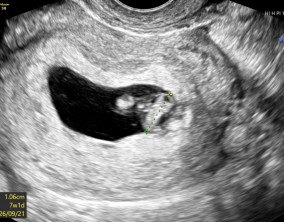

임신 수치 16, 9주차 기적의 기록

서울IVF에서는 단순히 배아 생성과 이식만 해주시는 것이 아니라, 제 생활 전반까지 신경 써주셨습니다. 휴식기에도 그저 기다리는 것이 아니라 항노화에 도움이 되는 링겔을 처방…